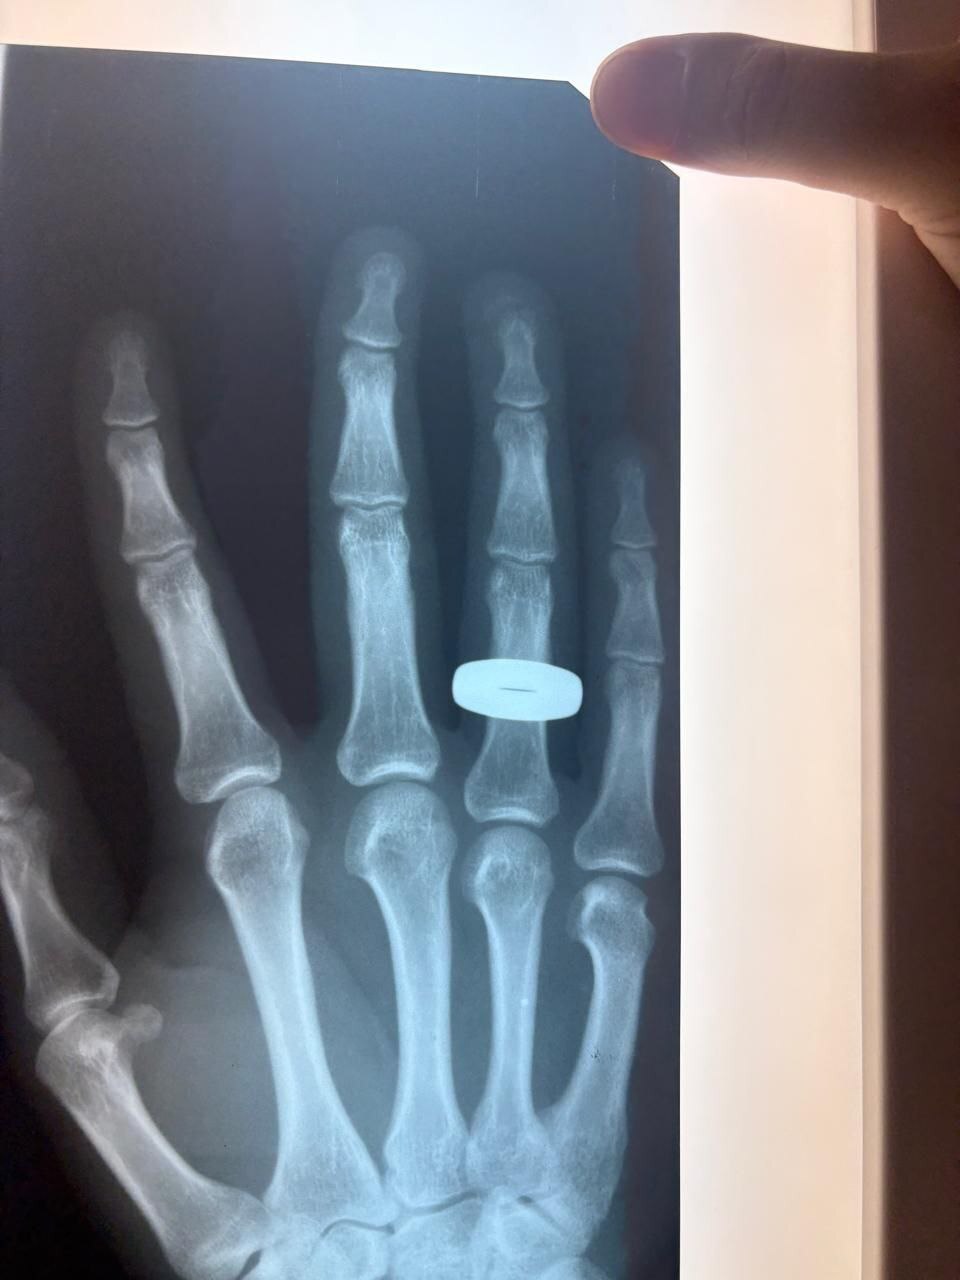

По информации медучреждения, 25 августа в приёмный покой хирургического отделения БГКБ обратился молодой человек с рваными ранами пальцев правой кисти. Как выяснилось, пациент был женихом, который в тот самый день со своей избранницей отправился на свадебную фотосессию в город Вольск.

В приёмном покое БГКБ ему оперативно оказали необходимую хирургическую помощь. После перевязки и получения рекомендаций врачей, стойкий молодожён, невзирая на суеверия о несчастьях до свадьбы, отправился догуливать свой торжественный день.